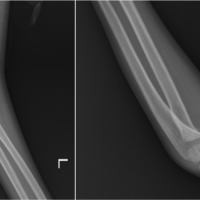

A 25-year-old male suffered an injury by a direct blow from the lower edge of steel cupboard, on the posterior aspect of his left ankle above the heel. He presented to us on the same day, after initially being treated at a local subcentre, with pain and a bleeding lacerated wound over the retro calcaneal region of his left ankle, and a sutured wound of 2 cm linear dimension (suturing done elsewhere), 5 cm proximal to the open wound. The patient was unable to walk. On examination, a lacerated wound of 4 cm * 2 cm dimensions was seen, about 2.5 cm proximal to the insertion of the Achilles tendon of his left ankle, with a palpable gap between the visible ruptured ends of the tendon. Thompson squeeze test and Matles test were positive. Toe raise on the affected side was absent. A palpable gap was also felt over the proximal sutured wound and a real-time ultrasonography (USG) revealed a complete tear of Achilles tendon in the proximal site as well (Fig. 1). The patient had no history of any medical illness. His routine blood investigations were normal. Informed patient consent was obtained for treatment. Both the wounds were explored on the operating table and a segmental Achilles tendon rupture was found (Fig. 2).

At 6-month follow-up, the tendon continuity was intact both clinically and radiologically (Fig. 5a and b), and the patient has been able to ambulate bearing full weight (Fig. 6) and with bilaterally comparable range of motion of the ankle (Fig. 7).